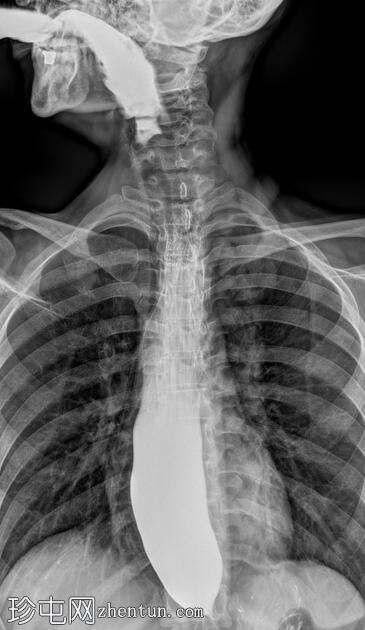

正位

食管扩张,远端平滑狭窄并呈锥形(鸟嘴状),符合贲门失弛症的特征性表现

食管黏膜形态正常,无异常或溃疡

未见食管裂孔疝

钡餐检查显示食管扩张,远端狭窄并呈锥形,形成符合贲门失弛症特征的鸟嘴状外观。